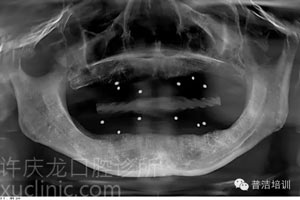

![]() |

上頜傾斜設計、下頜應用短植體X光 |